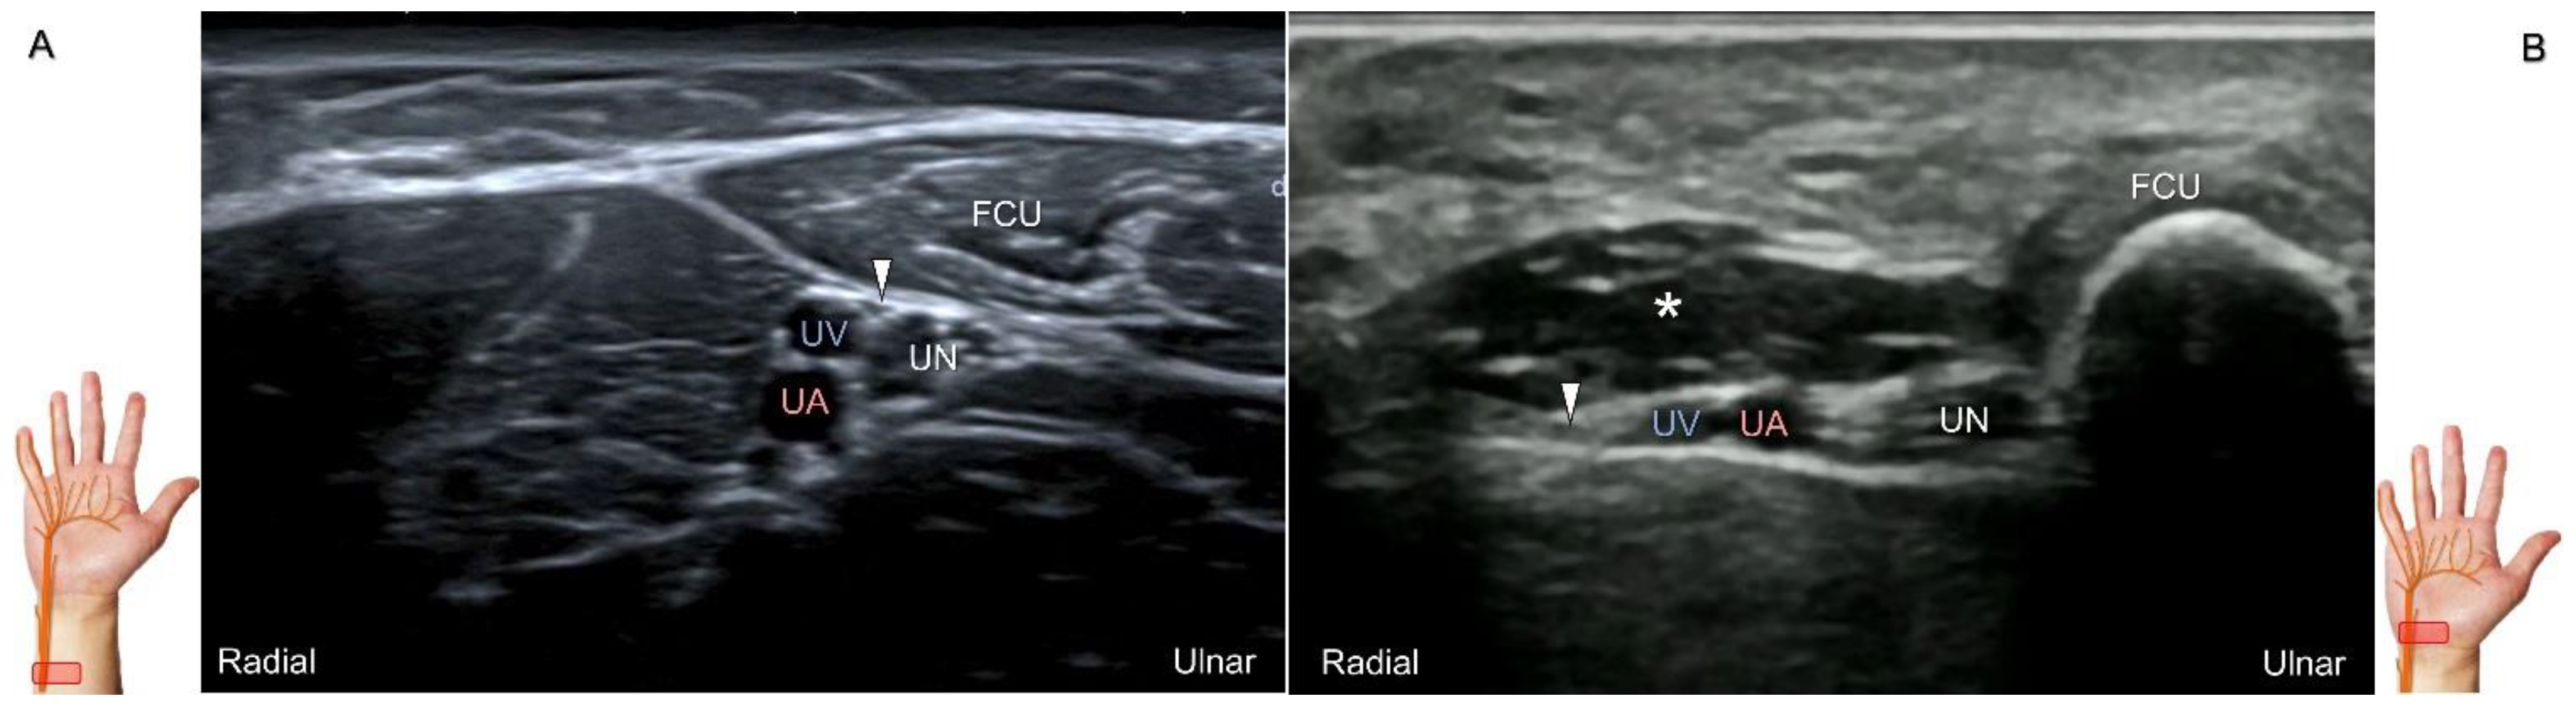

Scanning Technique

During scanning, the forearm is supinated with the transducer placed along the axial plane of the distal forearm. Moving the transducer more distally, the palmar ulnar cutaneous nerve can be seen as a single hypoechoic fascicle departing from the radial side of the main trunk near the bifurcating point for the dorsal ulnar cutaneous nerve (Figure 18A). It is crucial to apply light touch without compressing the adjacent vein, which can be used to highlight the nerve’s border.

Clinical Implication

The palmar ulnar cutaneous nerve has been associated with certain peripheral vascular disorders that can lead to arterial constriction and erythema over the hypothenar eminence [42]. The nerve may be persistently entrapped due to the presence of an accessory abductor digiti minimi muscle (Figure 18B) [42].

Figure 18. Sonographic imaging (short-axis view) of the palmar ulnar cutaneous nerve (A) and its entrapment in the presence of an accessory abductor digiti minimi muscle (B). Arrowhead: palmar ulnar cutaneous nerve; asterisk: accessory abductor digiti minimi muscle. UN: ulnar nerve; UA: ulnar artery; UV: ulnar vein; FCU: flexor carpi ulnaris tendon.